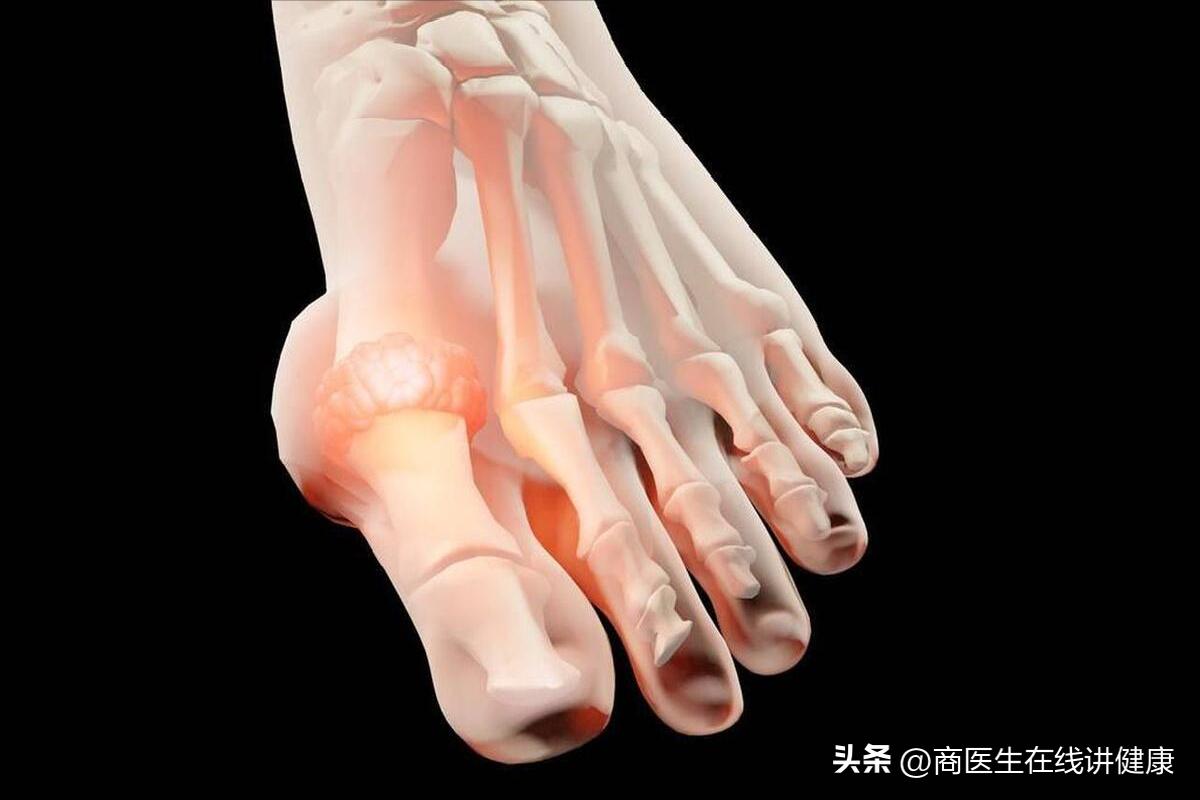

到我院后,医生询问张先生的 过往病史和主要病情 情况,以及做好基本体格检查后,怀疑张先生可能存在糖尿病足的情况,于是与张先生以及家属商量后,给予 血糖检测和足部X线平片检测,血糖检测结果显示10mmol/L,足部X线平片检测结果显示足部有周围末梢的骨质疏松,以及骨质水肿等不良营养情况的出现 ,检测结果均提示张先生患上了糖尿病足。

患有糖尿病足后,如果不能及时得到有效的治疗,很容易出现感染的情况,导致足部发生溃疡。 足部溃疡一般多见于前面的足底 ,是由于长期受到压迫而引起的一种疾病,一旦出现这种情况,很有可能就是糖尿病足溃疡,该类疾病具有一定的危险性,若不及时进行处理,任由疾病持续发展的话,很有可能会造成截肢的情况出现。